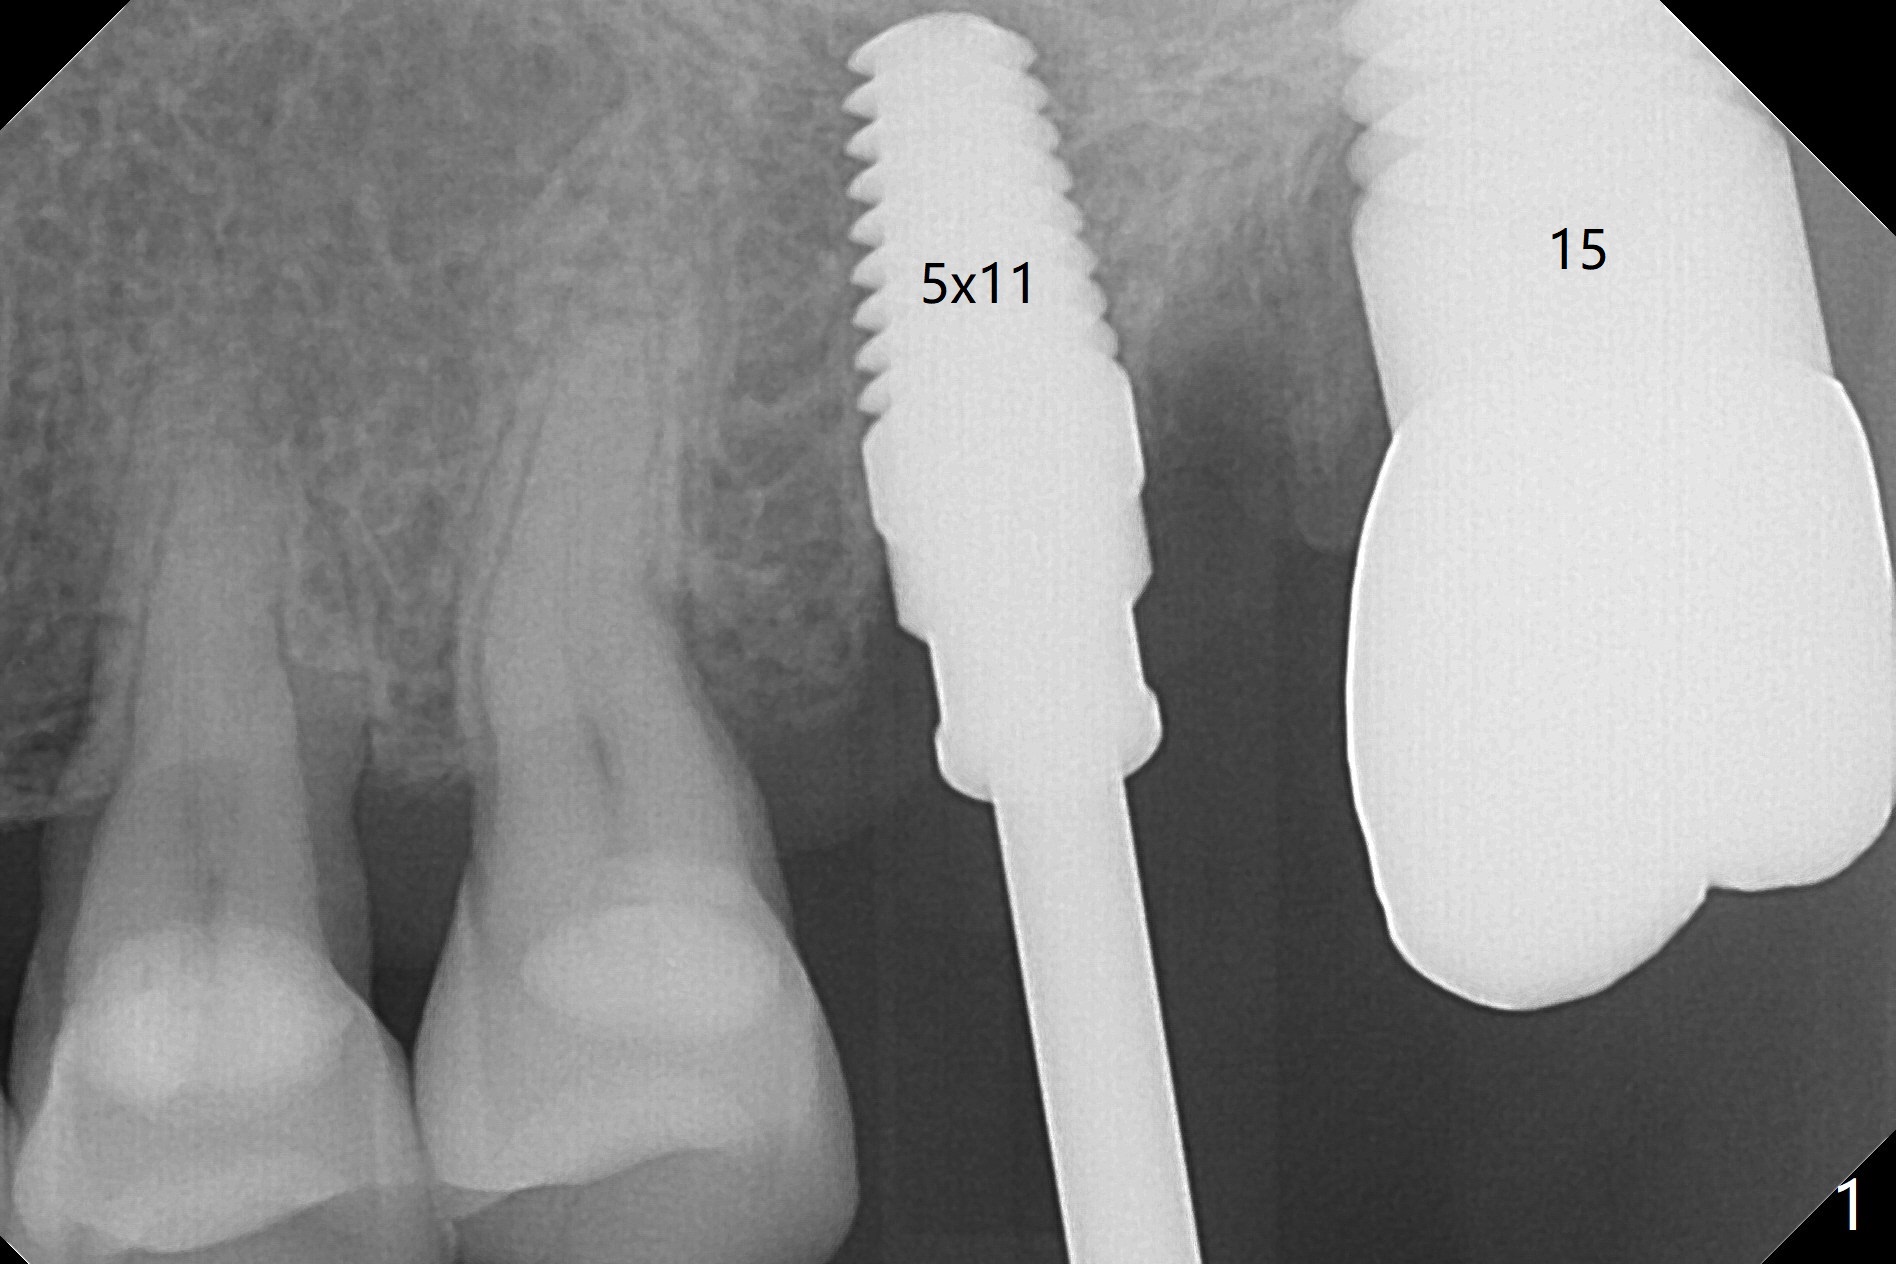

After osteotomy with guide at #14 (4.5x7.3 mm last drill with 1 O-ring/10.5 mm offset for bone-level implant), a 5x11 mm tissue-level tap is used with allograft for sinus lift (Fig.1). With one more round of allograft for sinus lift, a 5x11 mm tissue-level implant is placed with ~ 50 Ncm (Fig.2). CBCT 3-D images (Fig.3 (palatal view), 4 (distal view) (D: distal)) and coronal section (Fig.5 (P: palatal)) show the bone graft in the sinus (*). The patient returns for restoration 5 months postop in spite of running out insurance benefits because of discomfort with the immediate provisional. When the latter is removed (Fig.6), the gingiva is erythematous. It appears that the implant was placed deep. The abutment is removed for easy local oral hygiene. A healing cuff will be used or the implant will be reversely torqued. If the former is placed, a 4 mm longer abutment (4.5x9 mm) should be used to increase crown retention using temp bond . In fact the provisional forms a nice gingival cuff before cementation (Fig.7,8). Return to Upper Molar Immediate Implant, Prevent Molar Periimplantitis (Protocols, Table), Trajectory 18 Xin Wei, DDS, PhD, MS 1st edition 04/22/2019, last revision 02/28/2020